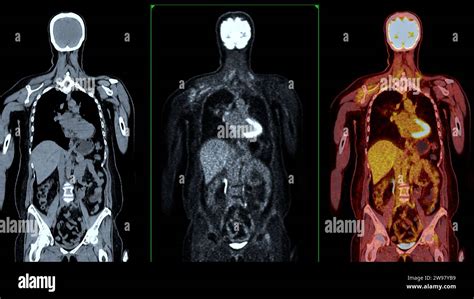

PET Scans: Metabolic Activity

Positron Emission Tomography (PET) scans detect the metabolic activity of cells. Cancer cells typically metabolize sugar at a higher rate than normal cells, making them "light up" on a PET scan. This is particularly useful for detecting distant spread (metastasis), assessing the overall extent of the disease, and monitoring how well treatment is working by seeing if tumor activity decreases. Often, PET scans are combined with CT scans (PET-CT) for both anatomical and functional information.